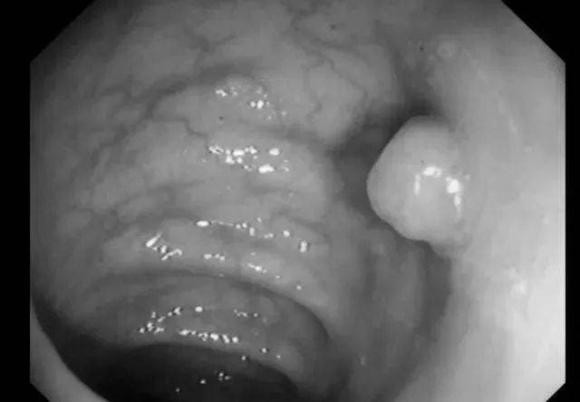

"Phần còn lại" của polyp thực sự có nghĩa là dư thừa, đó là phần thực vật thừa trên niêm mạc ở bề mặt bên trong của ruột. Trên thực tế, nó là một "vết sưng thịt" trên bề mặt niêm mạc ruột già.

Nói một cách chính xác, polyp đại trực tràng là những tổn thương nhô cao từ bề mặt niêm mạc ruột đến khoang ruột, đây là bệnh thường gặp, hơn 70% trong số đó là polyp tuyến.

Polyp đường ruột